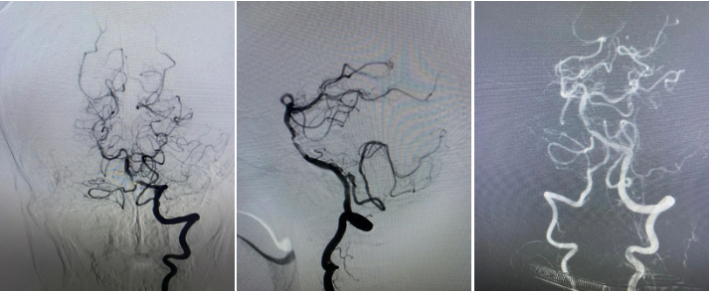

患者SCY,M59Y。2020年07月06日患者因症状性基底动脉重度狭窄,在外院行球囊扩张支架植入术。术中应用2.0mmx15mm Gateway球囊扩张,植入Enterprise 2 4.0mmx23mm支架,术后狭窄改善良好,患者无不适。规范应用双联抗血小板聚集治疗。

2020.07.10晚,患者术后第4天逐渐出现意识迷糊,嗜睡,考虑支架闭塞可能。遂急诊造影示:支架内血栓闭塞,意识模糊,危在旦夕,外院兄弟果断尝试再通,导丝导管通过后血流线样再通,撤回微导管注射替罗非班,血流难以维持。

再次尝试通过导丝导管,支架移位变形严重。